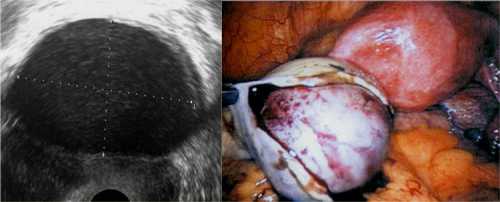

При возникновении резких болезненных ощущений и других подозрительных симптомах лучше всего сразу обратиться к врачу гинекологу. Методы леченияфолликулярной кисты яичника зависит от размеров образования. Кисты размером до см, как правило, не лечат. В большинстве случаев они сами рассасываются перед менструацией. Специалисты оставляют такие новообразования под наблюдением. Народное лечение фолликулярной кисты яичника используется, если ее размер не больше см. Обычно такие кисты также имеют свойство рассасываться. И для того, чтобы не возникало рецидивов, врачи могут предложить использовать гомеопатию и народную медицину. В более сложных случаях используют лечение препаратами. Это могут быть гормональные средства, противовоспалительные медикаменты или витаминные комплексы. Часто врачи назначают оральные контрацептивы для того, чтобы восстановить гормональный фон. Однако прием таких лекарств возможен только после проведения анализа крови на гормоны , Если кистозное образование продолжает расти и его размер становится больше см, то используется хирургическое вмешательство. Чаще всего используется лапароскопия. У женщин яичники работают поочередно. Поэтому в оплодотворении участвует только один из органов. И, если в нем образуется киста, то процесс оплодотворения становится невозможным до тех пор, пока она не исчезнет. Иногда это новообразование возникает в яичнике уже беременной женщины. Однако это очень опасно для малыша. И если ее не удалить, то такое состояние может привести к выкидышу или внутриутробной гибели плода.